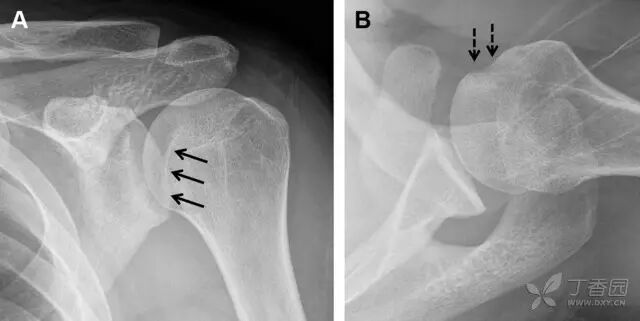

23 单纯肱骨大结节骨折

与其它肱骨近端骨折不同,单纯肱骨大结节骨折常发生于年轻人。肱骨大结节骨折常由撞击或剪切/撕脱损伤所致:

撞击包括直接撞击、肩峰撞击、上关节盂撞击(极度外展时);

剪切/撕脱损伤常发生于肩关节前脱位。

在常规前后位片上,大结节与肱骨头重叠,骨折不易发现,外旋位前后位片有助于诊断。

图 1 大结节骨折。(A)脂肪抑制序列斜冠状位 MRI,显示肱骨大结节线性骨折无移位(箭头)与周围骨水肿;(B)外旋位前后位(AP)片,证实大结节骨折(箭头),典型的骨折愈合过程中的骨吸收表现;(C、D)初诊时内旋位、外旋位前后位片,初诊时漏诊,仔细回顾影像,内旋伞下可见双密度影(椭圆),骨皮质中断(箭头)

肩胛骨几何形状复杂,受到邻近其它骨性结重叠阻挡,且肩胛骨骨折少见,因此容易漏诊。当存在解剖变异时,诊断更为困难。

图 3 肩胛骨骨折正侧位片:由于骨块的叠加,(A)前后位片示「V」形高密度影(*),肩胛颈下方可见骨皮质碎片(箭头);(B)侧位片示骨皮质中断,骨折段移位,但由于肱骨的重叠遮挡,决断往往比较困难

喙突骨折可发生于直接暴力、肩关节脱位过程的肱骨头撞击、以及撕脱骨折(肱二头肌短头、喙肱肌)。

其中喙突基底部骨折最多见,常发生于直接暴力或肱骨头前脱位,骨折可延伸至关节盂。

而撕脱骨折多为喙突尖部的骨折。需要加拍腋位和 Stryker 位片(X 射线束以喙突为中心并头倾 10°,手臂外展,这样可以避开骨性结构的阻挡)。

有时,负重位片可发现并存的肩锁关节脱位,将有助于诊断。

图 4 喙突骨折。66 岁男性患者,射击后右肩前方疼痛。(A)内旋位前后位片投影隐约可见喙突基底部骨折(白色箭头),(B)外旋位前后位片投影结构存在重叠,(C)腋位投影时可良好显示。(D~F)喙突骨折伴 Hill-Sachs 损伤:肩关节脱位后慢性疼痛,喙突骨折块(*)向前外侧移位(双箭头),在外旋前后位(D)及腋位(E)片上均可显示,在内旋位前后位(F)片上,喙突被遮挡,但可见肱骨头 Hill-Sachs 损伤。(G、H)喙突骨折伴肩锁关节脱位,肩锁关节分离(白色双箭头),而喙锁间距正常(黑色的双箭头),应警惕喙突骨折。(I)喙突与肩峰骨化中心:对于未成年人,喙突与肩峰骨化中心可同时存在,易与骨折混淆,此时,拍对侧的 X 线片对比将有助于诊断。

肩峰骨折为高能量损伤,多由直接暴力导致,好发于中青年患者,多伴有肩关节其它结构损伤。有必要拍摄 Rockwood 位(前后位片,X 线束尾倾),特别有利于显示肩峰下部及肩峰下间隙。

图 5 肩峰骨折。内旋位前后位(A)片上,骨折线几乎被喙突完全遮挡, 但是在标准前后位(B)和腋位(C)片上可见骨折线

肩关节是最容易脱位的关节之一,肩关节脱位常伴随其它结构的损伤,如血管神经损伤、肩袖损伤、盂唇损伤、Bankart 损伤等。脱位本身诊断往往是明确的,容易被忽略的是其继发的伴随损伤。

需要仔细评估肱骨头、大结节、关节盂边缘、肩峰、喙突等结构。典型的 X 线投射角度包括:内旋位前后位片、外旋位前后位片(Grashey 位)、侧位(肩胛骨 Y 位)、腋位片以及改良腋位片。

图 6 肩关节前脱位伴有 Hill–Sachs 和 Bankart 损伤:(A~C)肱骨头后外侧撞击骨折,白色箭头所示为骨折的内侧边界;(A)内旋位前后位片,(B)「V」形压缩骨折的下边界(虚线短箭头),(C)Garth 位(轴向投影)示 Hill–Sachs 损伤(虚线和实线折箭头),特别是对骨性 Bankart 损伤的诊断有帮助。(D、E)MRI 进一步证实了损伤

图 7 肩关节后脱位伴有反 Hill–Sachs 损伤。(A)外旋位前后位片可见一硬化带(黑箭头),此「凹槽征」与肱骨头关节面平行;(B)腋位片进一步证实了骨折的存在